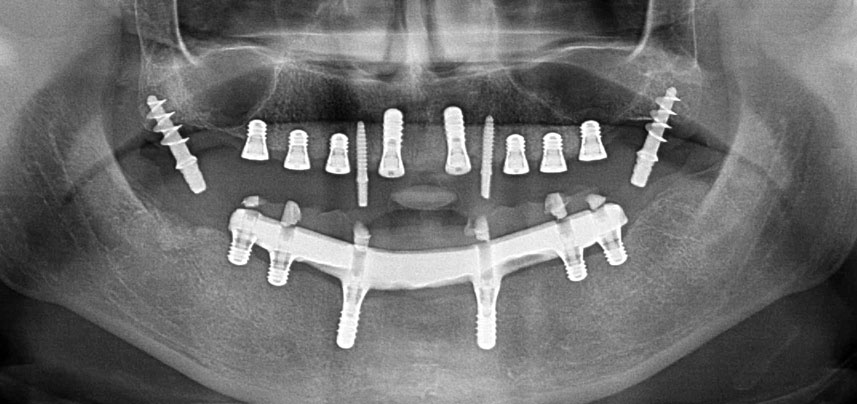

Три години по-късно е дошло времето за максиларна протеза от същия тип. Въз основа на планирането със CBCT, аугментацията на синусите е избегната с помощта на къси импланти и използването на хирургичен шаблон, за да се прехвърлят планираните позиции в алвеоларния гребен. (Фиг. 1 и 2).

Поради сравнително твърдата кост (D2) в тази област, 10-милиметровото имплантно ложе в позиции 11 и 21 беше завършено с ротационен дрил с диаметър 4 mm в комбинация с W&H хирургичен обратен наконечник WS-75 L, W&H имплантологичен мотор Implantmed и опционалния W&H Osstell ISQ модул. За разлика от това, благодарение на меката кост, дисталните зони се подготвят до окончателен диаметър 3 mm, използвайки накрайник за Piezomed I3P. Имплантите най-накрая са поставени трансгингивално, за да остеоинтегрират за три месеца (Фиг. 6-10). Съществуващата протеза се фиксира на четирите временни импланта (Фиг. 8).

Избраната комбинирана препарационна процедура с ротационно финализиране на предните имплантни зони в твърда кост се оказва ефективна, докато пиезоелектрическата препарация е оптимална за задната мека кост с ниска остатъчна костна височина.